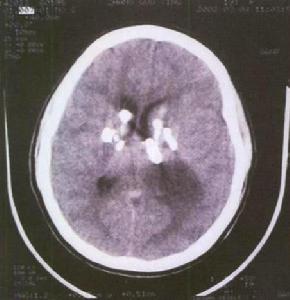

6.腦CT檢查CT對顱內腫瘤特別是幕上腫瘤的診斷,比其它輔助診斷技術有更多的優點是較為理想的檢查診斷方法。